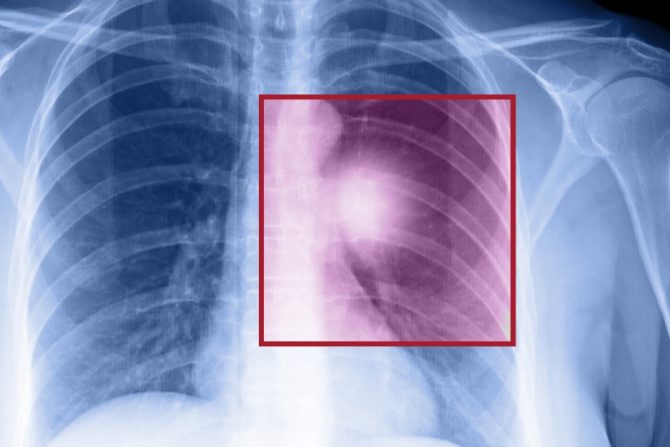

Mitovi i zablude o raku - dijagnozi koja izaziva toliko straha i jakih emocija, mogu da budu čak i gori od realnosti. Termini rak ili karcinom su toliko moćni da često mogu da parališu čoveka, i to pre svega zbog onoga "što su čuli" a ne zbog onoga što je zapravo realno.

Dr Michael McNamara onkolog sa Cleveland Clinic naglašava da mnogi ljudi imaju unapred stvorene ideje o karcinomu i uglavnom su to netačni podaci kojima raspolažu, a koji su često strašniji od stvarnosti sa kojom se obolele osobe suočavaju. Stručnjaci ističu da su nebrojeni mitovi i zablude o raku koji kruže među ljudima, vrlo često otežavaju lečenje obolelih, a najčešći su ovih 6.